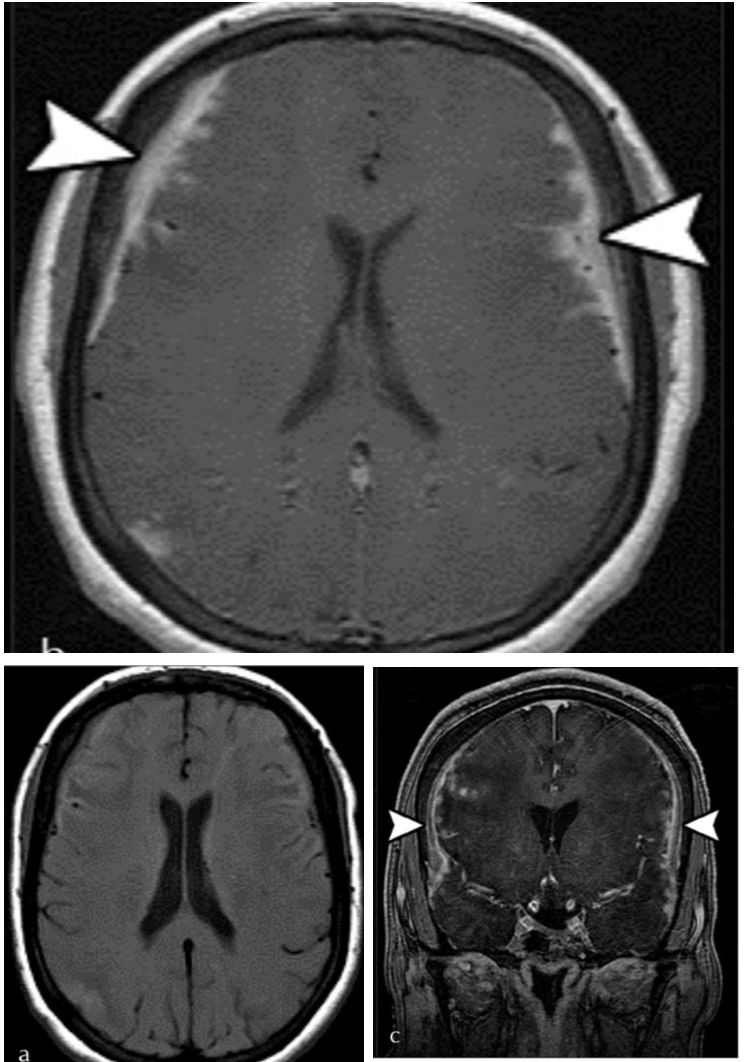

增强序列可见双侧额叶软脑膜明显强化并沿软脑膜侵入沟回,左侧颞顶交界区小片状强化;冠状位及FLAIR可见皮层皮下之白质亦有波及。该病例只有磁共振,且只有FLAIR和增强两个序列,但给人的信息量并不少:脑膜尤其是软脑膜受累突出,伴有皮层、实质损害,强化明显。感染、肿瘤、非感染性炎症都有可能,到底是什么呢?

诊断: 神经结节病

结节病是一种病因不明的多系统肉芽肿性炎症性疾病,年轻人多见。全世界的发病率各不相同,约为10-20/100,000人。它主要影响肺,皮肤和眼睛,神经系统受累约占5-20%。可以说神经结节病是罕见病中的少见表现,但其影像学具有一定的特点,也容易与其他疾病混淆,了解了这些特点在日后不期而遇时不会让它从眼皮下溜走。神经结节病影像学最突出的特点是软脑膜受累,但只知道软脑膜是不足以全面掌握神经结节的影像学表现,关于神经系统其他受累部位及鉴别诊断如下图:

这里摘选几张有代表性的影像:

➤脑实质受累(fig3:延血管间隙播散的炎性肉芽肿改变;fig5:脑白质病变):